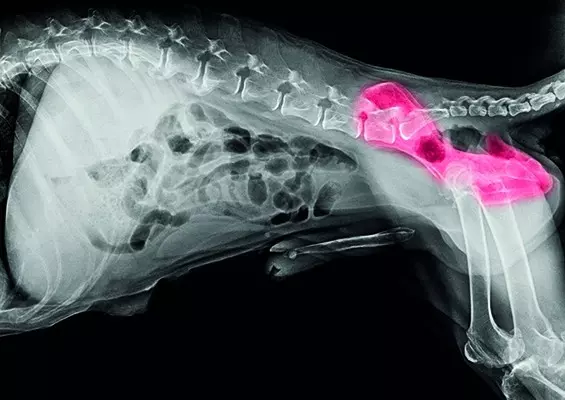

OTYŁOŚĆ U ZWIERZĄT

Problemy z nadmierną masą ciała ludzi nie są niczym nowym – już Hipokrates odkrył związek między otyłością a śmiercią. Jak się jednak okazuje, jest to najczęściej występująca choroba żywieniowa już nie tylko wśród ludzi, ale również wśród zwierząt towarzyszących, takich jak psy i koty. Otyłość jest poważnym schorzeniem, które znacząco zwiększa ryzyko wystąpienia chorób przewlekłych, obniża komfort życia oraz jego długość. Otyłość charakteryzują wzrost i nadmierne nagromadzenie tkanki tłuszczowej, które pojawia się w miejscach jej anatomicznego występowania lub w postaci guzów dużej wielkości, mających negatywny wpływ na organizm.